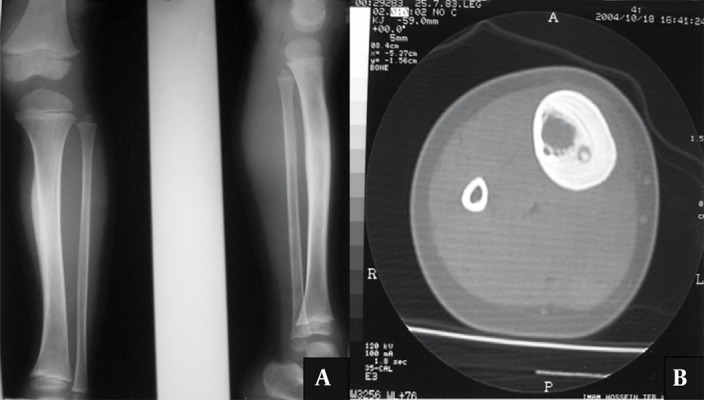

6.1 Radiografía simple

- 🩻 Nidus radiolúcido (3–15 mm) con esclerosis reactiva variable y a veces desproporcionada.

- 🩻 Puede ser difícil de ver, sobre todo al inicio o en localizaciones complejas.

6.3 Tomografía computarizada (TC)

- 🩻 Prueba de elección: cortes finos (1–2 mm) para visualizar el nidus.

- 🩻 Fundamental para planificar RFA o cirugía.

Hallazgo radiológico característico